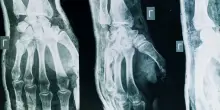

Artrosi, tutti i segnali per riconoscerla

L'artrosi è una patologia cronica molto comune che causa una ridotta funzionalità articolare, accompagnata da dolore. Può colpire la colonna vertebrale, le dita, le ginocchia e le anche. Può manifestarsi a qualsiasi età, ma l'invecchiamento rimane il principale fattore di rischio. Ecco una spiegazione.